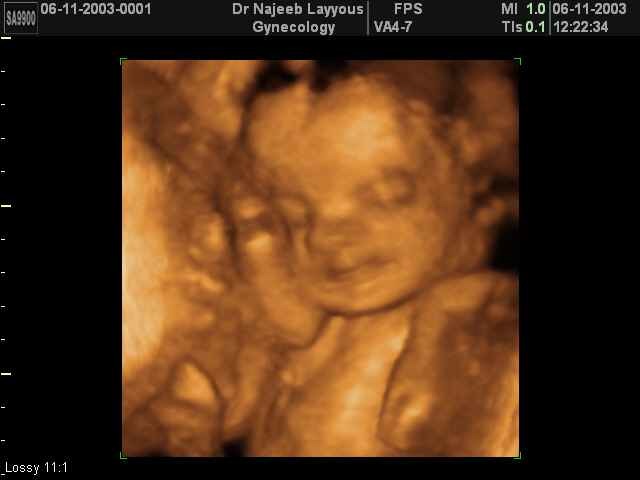

What happens during weeks 25–28 of pregnancy?

The eyes can open and close and sense changes in light.

Lanugo begins to disappear.

The fetus kicks and stretches.

The fetus can make grasping motions and responds to sound.

Lung cells begin to make surfactant.